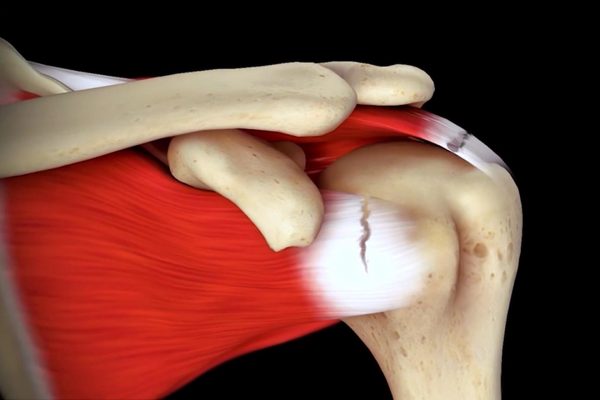

Pectoralis Minor Tenotomy in Shoulder Arthroplasty: A Novel Therapeutic Approach

While further studies are certainly imperative, in the absence of any observed short-term complications, pectoralis minor tenotomy appears to be a safe and potentially effective mitigation strategy for addressing distal neuropathy and improving scapulohumeral rhythm in reverse shoulder arthroplasty procedures.